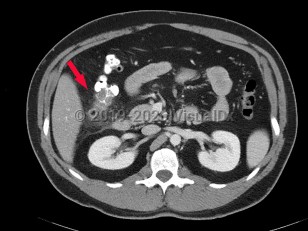

Ureteral calculus